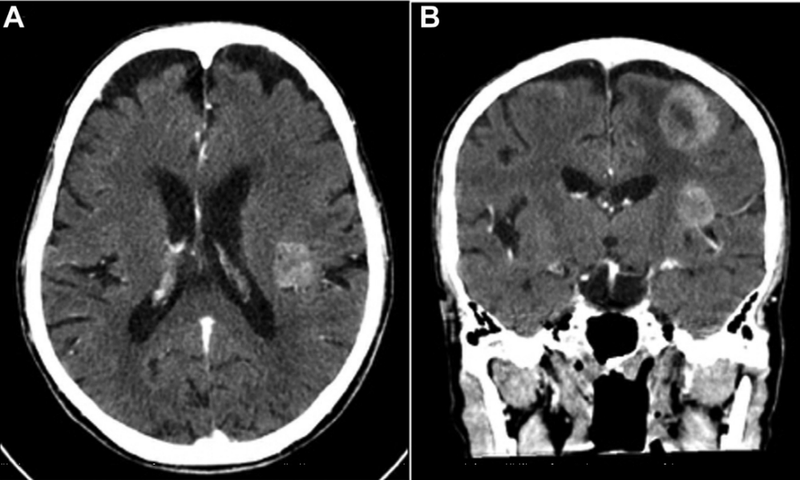

脑部CT扫描显示左侧顶叶内可见多发大肿块,增强后显示伴有不均质强化,肿块局部压迫效应明显,伴有血管源性水肿(见下图A和B)。